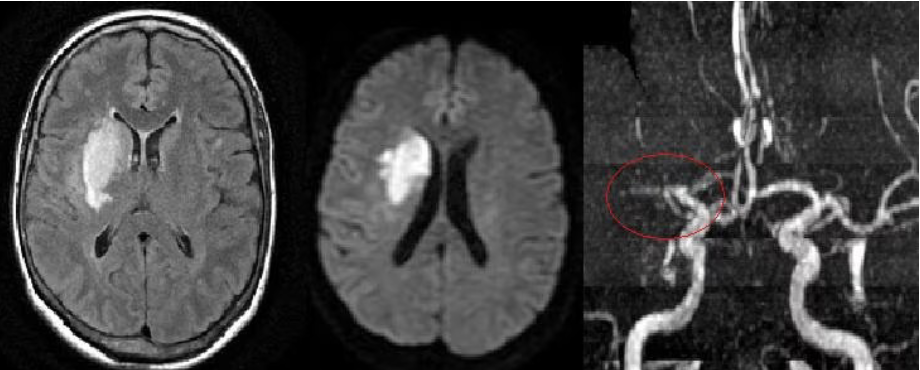

what are the 2 types of stroke?

ischemic stroke

hemorrhagic stroke

what causes ischemic stroke?

Caused by a blockage (e.g., thrombus or embolism)

• MCA, ACA, PCA & Basilar

what causes Hemorrhagic stroke?

Caused by bleeding (e.g., aneurysm rupture or trauma)

• Circle of Willis and Deep Arteries